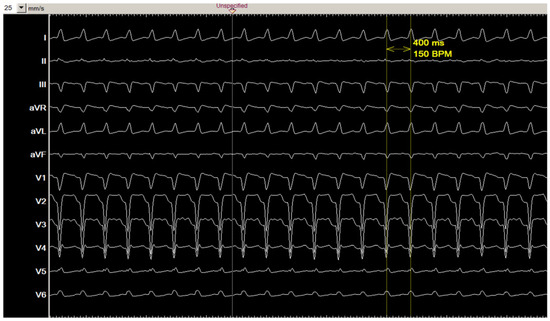

2.1. Clinical Presentation

2.4. Outcome